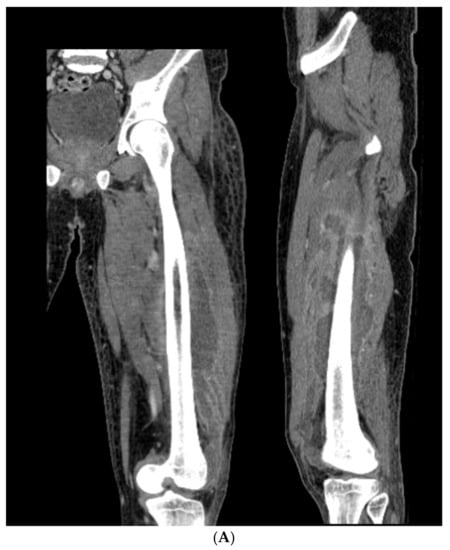

3.4. Case 4-Infected Malunion-Nonunion Femur Correction: True Dome Osteotomy

A young adult male presented new-onset diabetic ketoacidosis and sepsis. The study revealed a large thigh abscess circumferentially surrounding the left femur (Figure 9A). No other source was identified during workup. The patient underwent multiple debridements, and initially, a cortical window was made for the egress of intramedullary purulence. Subsequent debridements revealed extensive osteomyelitis. During debridement with intramedullary antibiotic nailing, the femur fractured and was eventually resected to attain source control (Figure 9B). A 13-cm segmental defect was stabilized using an antibiotic-coated locked nail with the surrounding antibiotic bone cement spacer Figure 9C). The CORA analysis revealed a five-degree varus deformity and no significant sagittal plane deformity. After source control with intravenous antibiotics and a 3-month course of oral antibiotics, the workup, including a biopsy and culture, resulted in no growth and no sign of ongoing infection. A bifocal true dome osteotomy with intercalary cortical allograft was chosen based upon a low likelihood of compliance with bone transport. A standard lateral approach elevating the vastus lateralus was used to access the femur. Reverse reamers and standard acetabular reamers were used for mating the bone surfaces (Figure 9D). The varus alignment was addressed using a blocking screw as the nail was passed; no gap was produced at the osteotomy due to its true dome shape. The dome osteotomy interfaces were autografted and compressed with a magnetic motorized nail, with additional compression at the subsequent outpatient visits (Figure 9E). The patient had soft tissue and allograft interface healing without incident and returned to gainful employment (Figure 9F).

Figure 9.

(A) A young adult male presented new-onset diabetic ketoacidosis with sepsis. He was found to have a large spontaneous left thigh abscess, as seen on CT imaging. (B) Multiple surgeries resulted in a femur fracture and subsequent segmental resection of approximately 13 cm of the patient’s femoral diaphysis. (C) The patient eventually attained source control with resection, antibiotic spacer, and an antibiotic coated nail. Patient has a 5-degree distal varus deformity. (D) The patient underwent a true dome osteotomy of the proximal and distal ends of the allograft/host bone interfaces. Fresh frozen allograft preparation using a reverse reamer is shown prior to implantation. (E) Motorized compression of the construct was employed with early and subsequent compression. Four-month follow-up showed restored neutral alignment, incorporation/interface healing of the dome osteotomy sites, bone regenerate across the interfaces, normal lab markers, and return to gainful employment. (F) Twelve-month follow-up continued to demonstrate interface healing without infection recurrence.